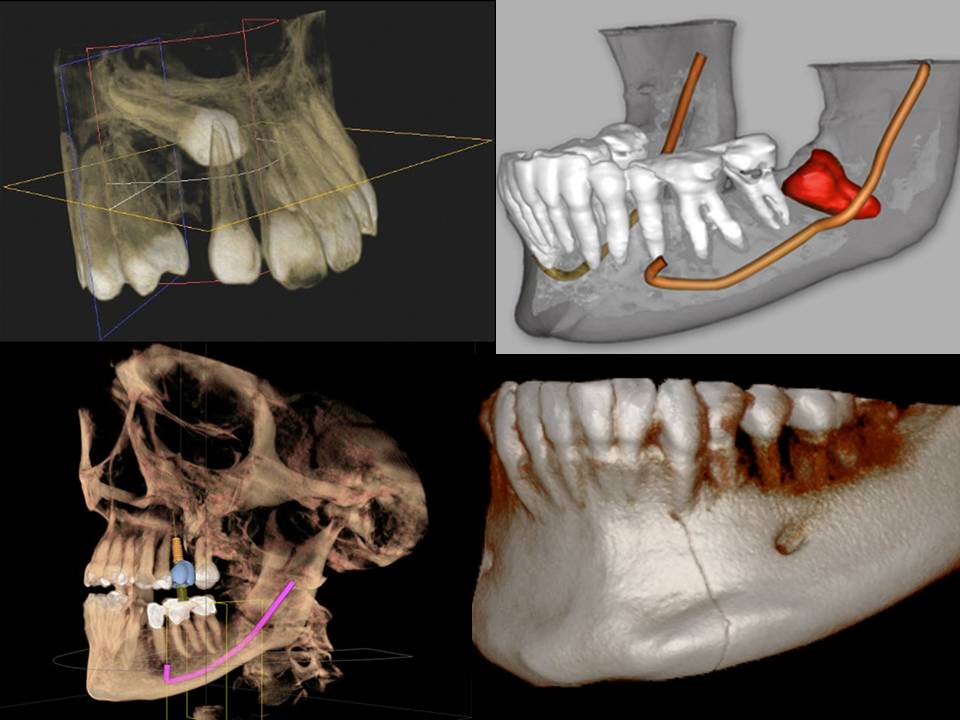

Компьютерная томография (КТ) - самое подробное, полноценное и комплексное исследование пациента, применяемое в стоматологической практике, и является неотъемлемой частью современной 3D-стоматологии. КТ позволяет врачу-стоматологу выявлять любые проблемы в зубочелюстной системе, вплоть до мельчайшего кариеса, невидимого в полости рта при классическом осмотре.

Vatech, используя технологию Green Technology, снизил уровень излучения в аппарате PaX-i3D без потери качества изображения.

Инновационная форма объема PaX-i3D обеспечивает сканирование в форме зубной дуги и показывает весь зубной ряд, в отличии от других аппаратов с аналогичным по размеру FOV (зоны сканирования). Обычно 10X8.5см достаточно для сканирования зубов мудрости. Тем не менее, когда они лежат на боку, существует высокая вероятность того, что они не попадут в зону сканирования. FOV в форме зубной дуги устраняет эту вероятность, показывая скрытую область.